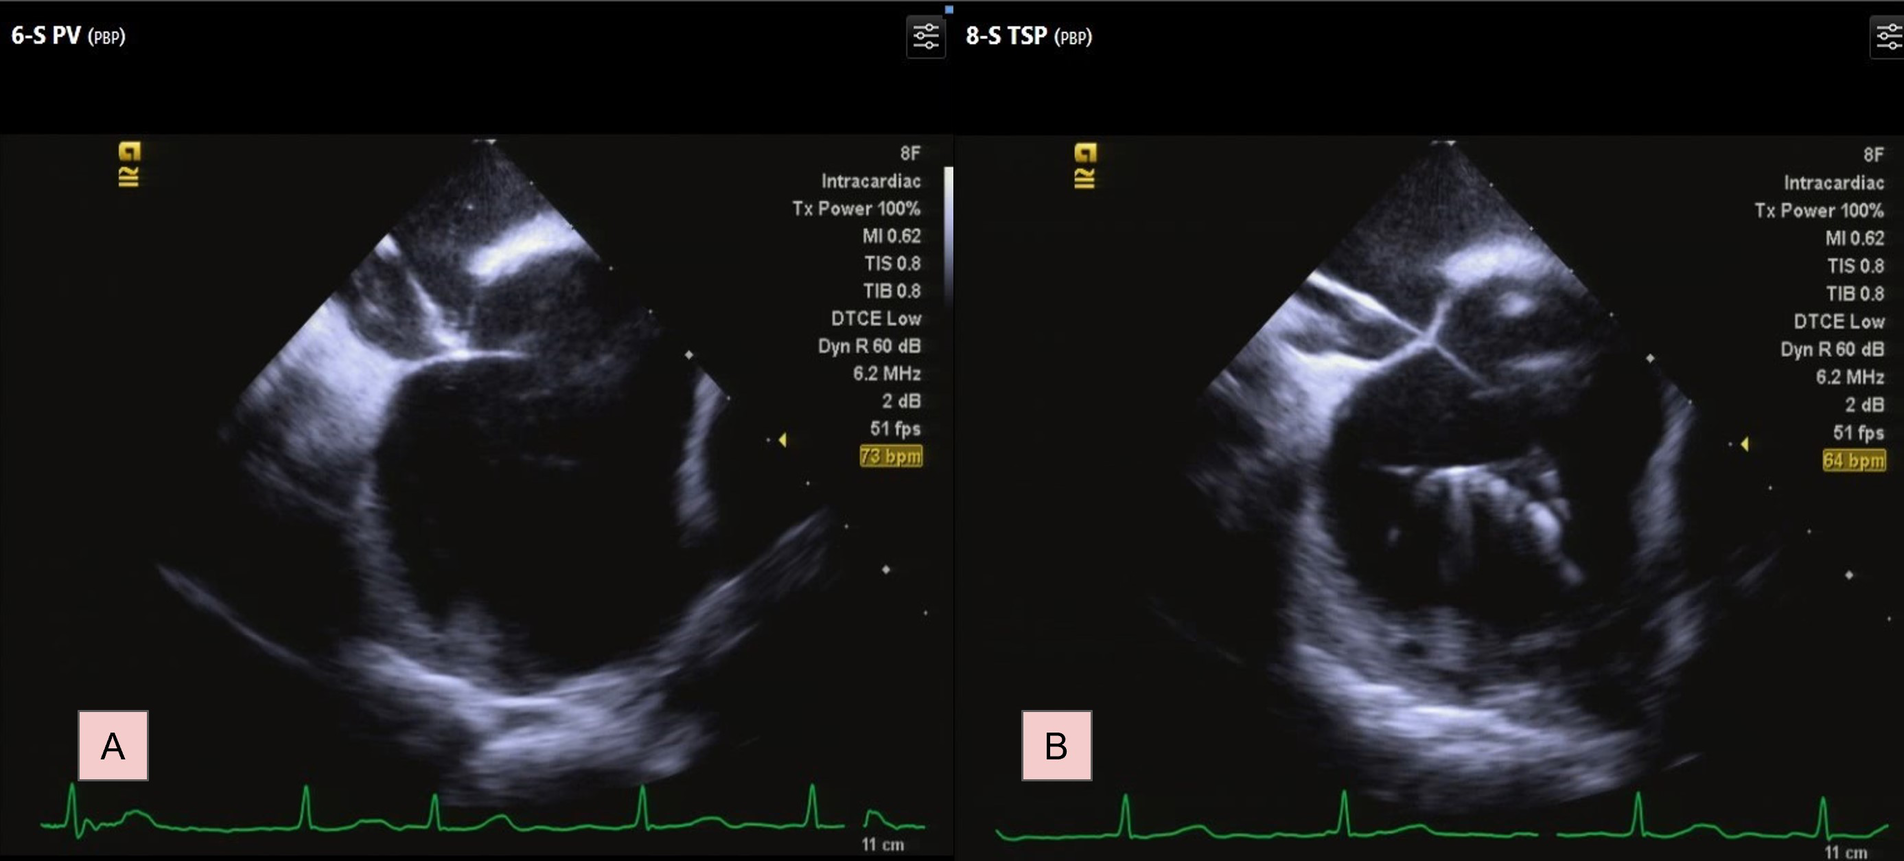

Under ICE guidance, the sheath and the GMS-1 wire were positioned against the septum. This was confirmed by the typical “tenting” appearance on echocardiographic imaging when slight pressure was applied to the septal wall (Figure 2A). The wire was then advanced through the septum into the left atrium (LA) using electrocautery technique with an energy of 30–35 W for less than 1 s under “dry cut” mode by ERBE VIO 10°C generator (ERBE Elektromedizin GmbH, Germany). Upon accessing the LA, the wire's tip immediately assumed a pigtail configuration, preventing further tissue penetration (Figure 2B; Supplementary Video S1). Subsequently, the SL0 sheath and its dilator were smoothly introduced into the LA. A second TSP with Vizigo (Biosense Webster) was done smoothly using the same technique. PVI was subsequently completed smoothly.

Figure 2

Transseptal process under ICE. (A) Identify the septum by typical tenting image. (B) The GMS-1 guidewire formed a pigtail shaped. For a complete video clip, please refer to Supplementary Video S1.